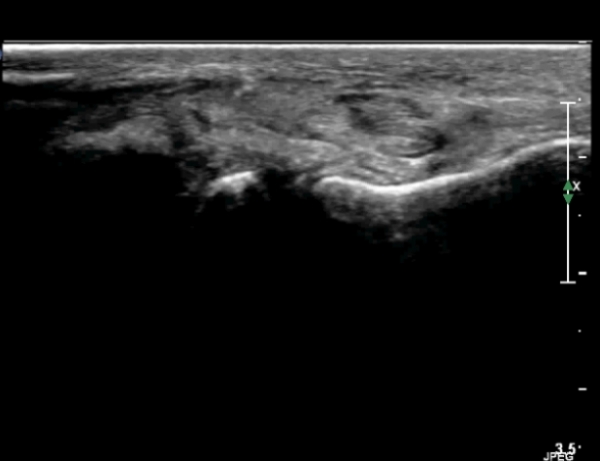

¹ß¸ñ ¾ÕÂÊ Á¾´Ü¸é°Ë»ç¿¡¼­ °üÀý³» ºÎÁ¾À» º¸ÀδÙ(»çÁø 1).

°üÀý³» ºÎÁ¾Àº ½É°¢ÇÑ ¼Õ»óÀ» ¾Ï½ÃÇÏ´Â ¼Ò°ßÀÌ´Ù.